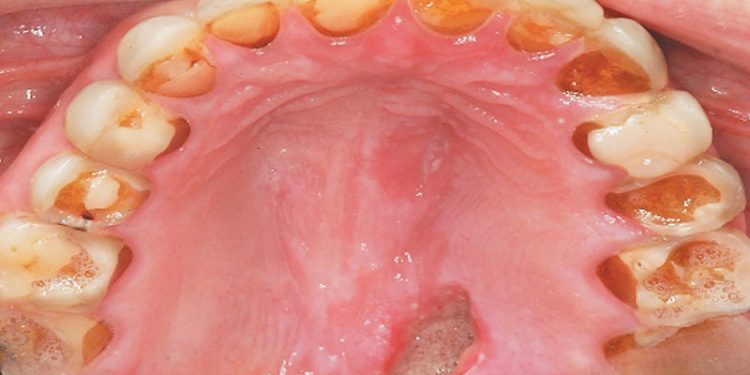

Bulimia or bulimia nervosa is a severe eating disorder that involves consuming copious amounts of food at one time. During an episode, those that binge has no control over their eating. Because of the worry of weight gain, they use unhealthy ways to lose weight.

According to NationalEatingDisorders.org, bulimia nervosa is a serious and often life-threatening eating disorder that is characterized by binge eating and then vomiting or other self-harming actions to undo the calories gained by the binge eating.

- Self-induced vomiting, especially after eating